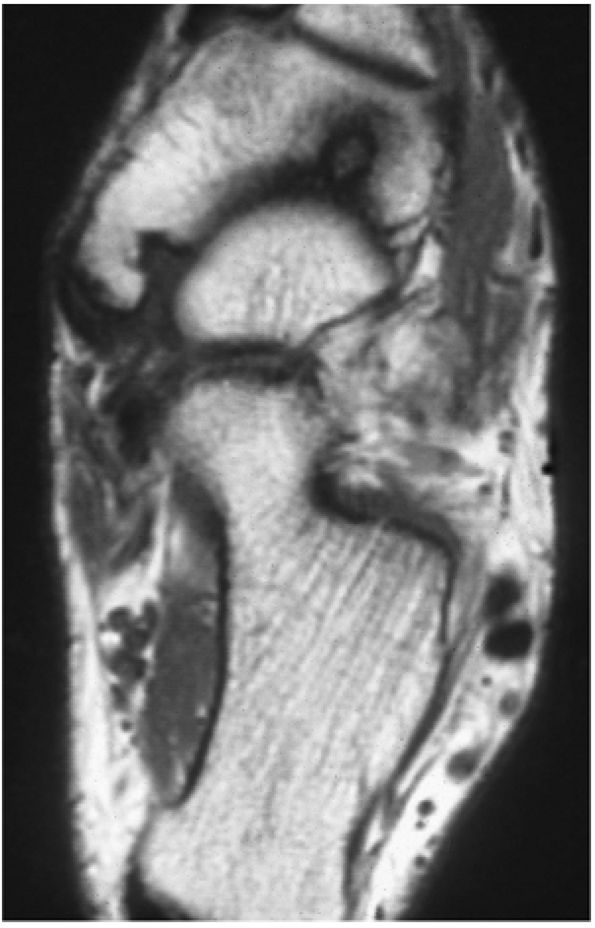

The spring ligament complex consists of three components: the lateral, intermediate, and superomedial oblique calcaneonavicular ligaments.

structures are critical static stabilizers of the medial longitudinal arch of the foot, providing support for the head of the talus at the talocalcaneonavicular joint (or acetabulum pedis). The other major stabilizer of the medial longitudinal arch, the PTT, is a dynamic stabilizer. Pathology of the spring ligament complex rarely occurs in isolation and is almost always associated with PTT dysfunction. Attention to the components of the spring ligament on routine MR imaging of the foot is important, since there is often a cascade of failures that can lead to or be seen with acquired pes planus deformity.